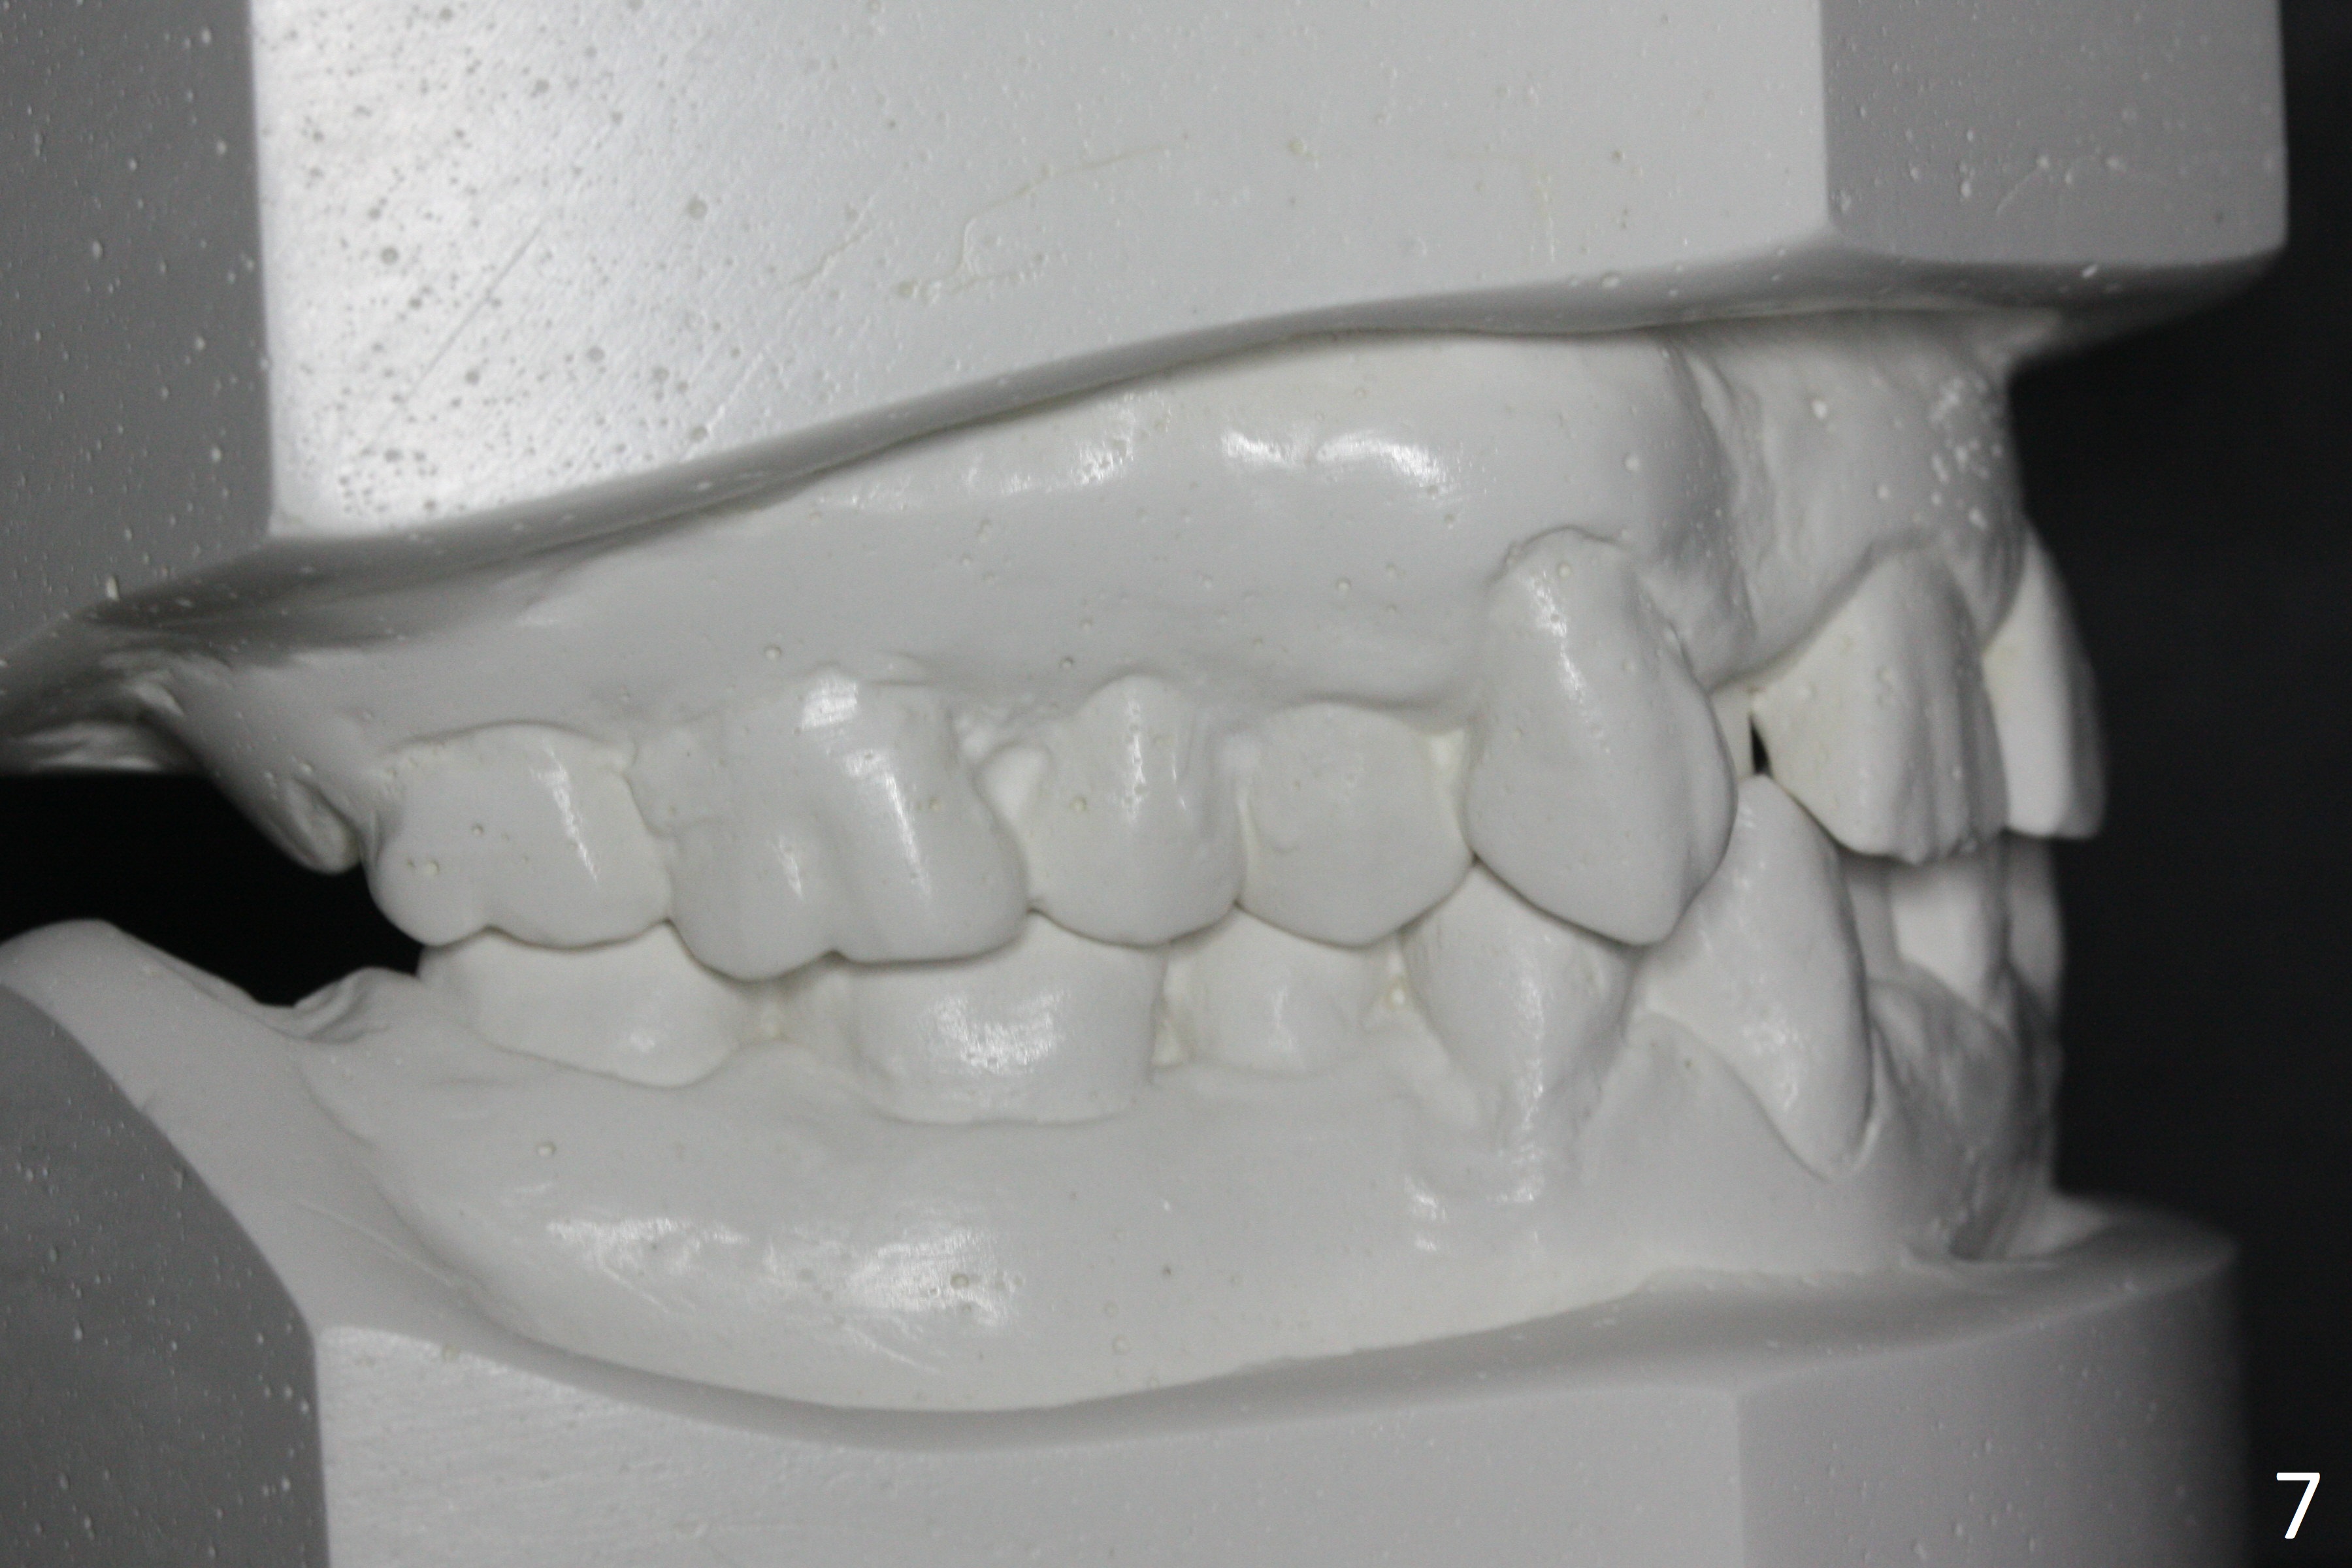

Enough Space For Crowding After Extraction? A 47-year-old man requests orthodontic treatment following SRP in other office (Fig.1-11). For severe crowding and midline shifting, extraction of four of the 1st bicuspids is imminent. Is it enough? To answer the question, model surgery is performed (Fig.12-16). 1st visit: periodontal maintenance, orthodontic consent (emphasizing oral hygiene) extract 4s and possibly L8s and separators. The beauty of this vist is that after local anesthesia and extraction including L8s, it is painless and easy to remove calculus from the proximal surfaces of the neighboring teeth. It is much easier to place separators after extraction. It is expected that there is no gingival erythema when the patient returns for bracketing. Take photos of UR3, similar to Fig.3. Molar banding is also anticipated to be easy with separator placement after extraction. Return to Ortho Cases Xin Wei, DDS, PhD, MS 1st edition 11/23/2017, last revision 04/28/2019